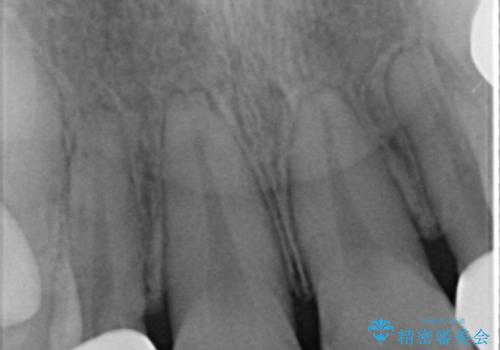

全顎的に歯並びにがたつきがあり、上の側切歯(上顎両側2)は生まれつき小さい歯(矮小歯)でした。

矯正治療後、矮小歯をセラミッククラウンにより理想的な歯の大きさに仕上げました。